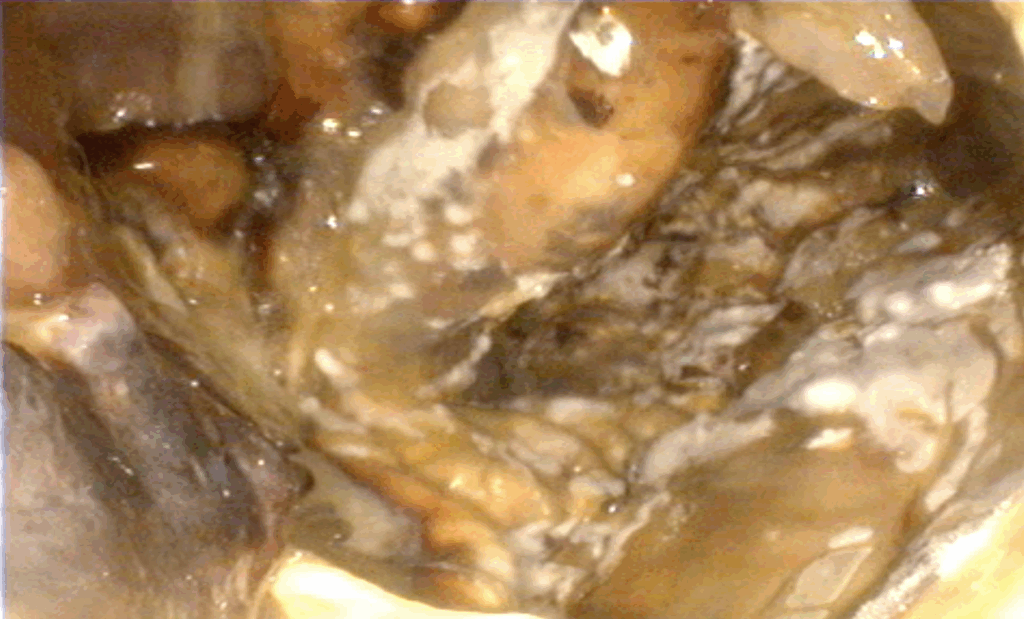

Jakmile se plíseň rodu Aspergillus uchytí ve vzdušných vacích, nalezne zde ideální místo k množení. Plísně mají rády teplo, a proto se obvykle usídlují v blízkosti velkých krevních cév, které vedou vzdušnými vaky. Tyto tepny jsou pro plísně zároveň ideálním zdrojem živin. Nejčastěji se plísně nacházejí v blízkosti vnitřní větve krkavice (obr. 3 a, b, obr. 4).